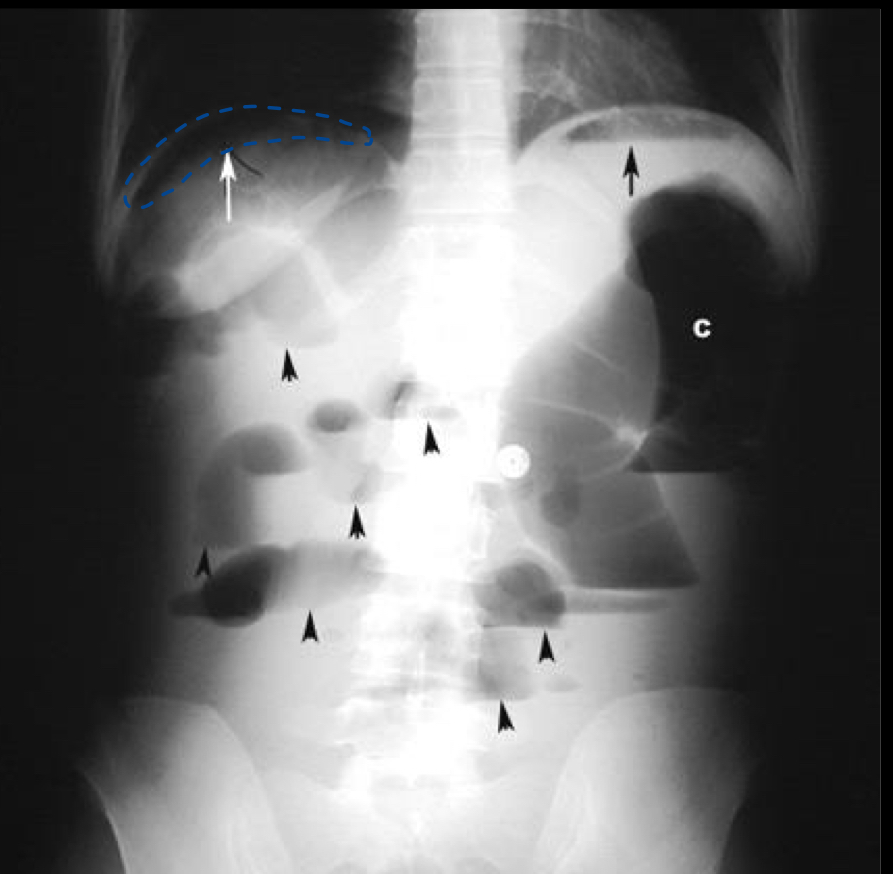

What is indicated by the top left arrow?

pneumoperitoneum

What is indicated by the top right arrow?

air in the stomach (normal)

What is indicated by the letter C

large intestine obstruction

What is indicated by the shorter black arrows?

small bowel obstruction

What is indicated by the red dotted lines?

What is indicated by the black arrow?

What is indicated by the white arrow?

(see double line in the stomach shadow area)